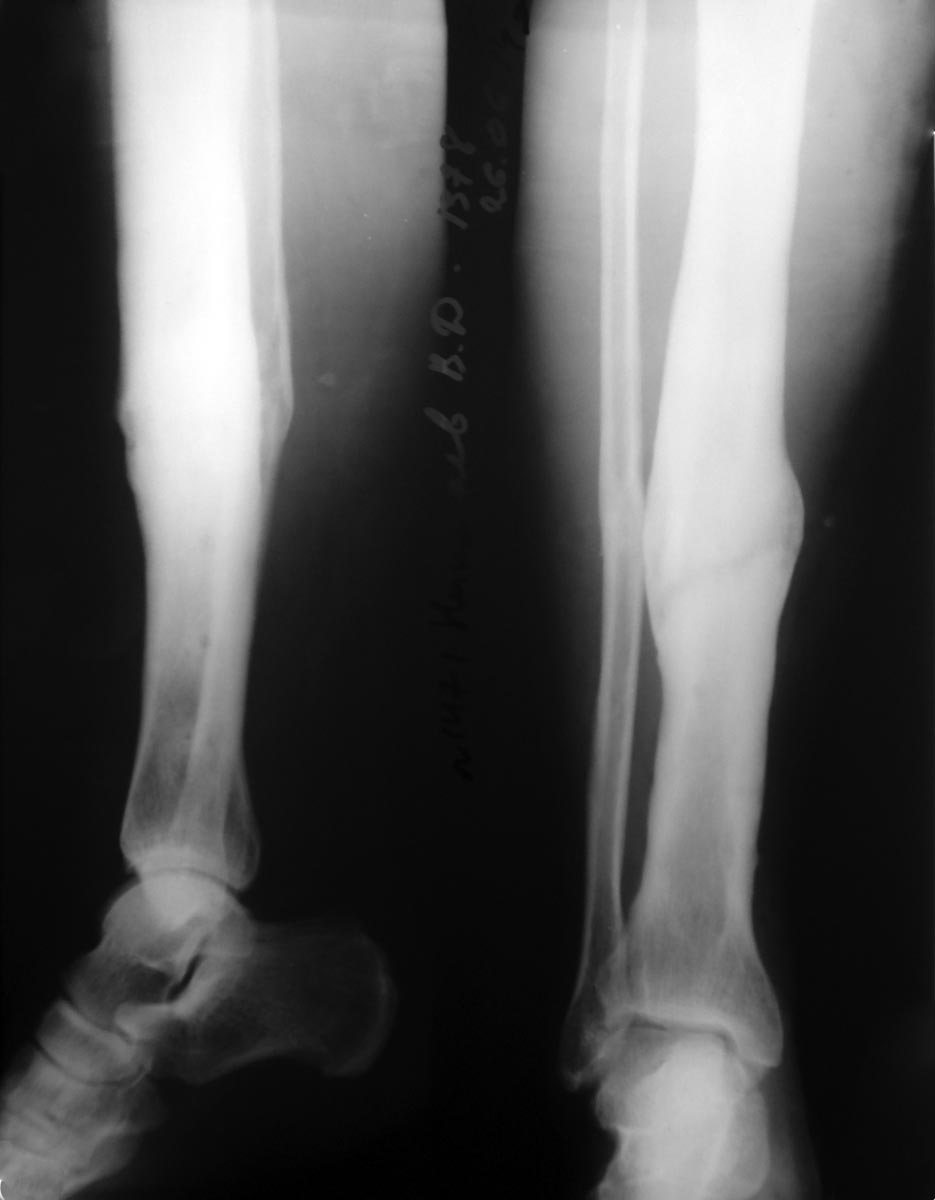

У меня недавно был на консультации подобный больной. 4 года назад ДТП, в

результате которого открытый оскольчатый перелом костей голени в средней

трети. Был установлен АВФ с переходом на БИОС. Через год после операции

открылся свищ в нижней трети голени в проекции блокирующих винтов. В

течение 3 лет свищ периодически открывается. Через 2 года после

появления свища была выполнена операция по удалению гвоздя. Но проблему

это не решило. Думаю о следующем плане обследования и лечения: 1. КТ

костей голени; 2. Фистулография; 3. Некрсеквестрэктомия с установкой бус

на 5 дней.

P.S. На рентгенограммах состояние на сегодняшний день